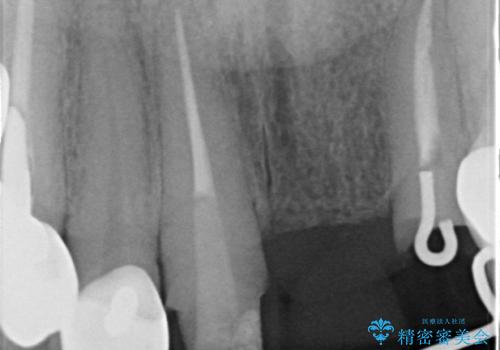

- 前歯の審美障害、見た目の改善を希望され来院されました。

歯肉縁下カリエスも認められるため、挺出を行いセラミックブリッジを審美的に新製します。

虫歯が深くなった場合、挺出や歯周外科を行い歯周組織の状態を改善することでより安定した状態で予知性の高いセラミックブリッジを製作することが可能となります。